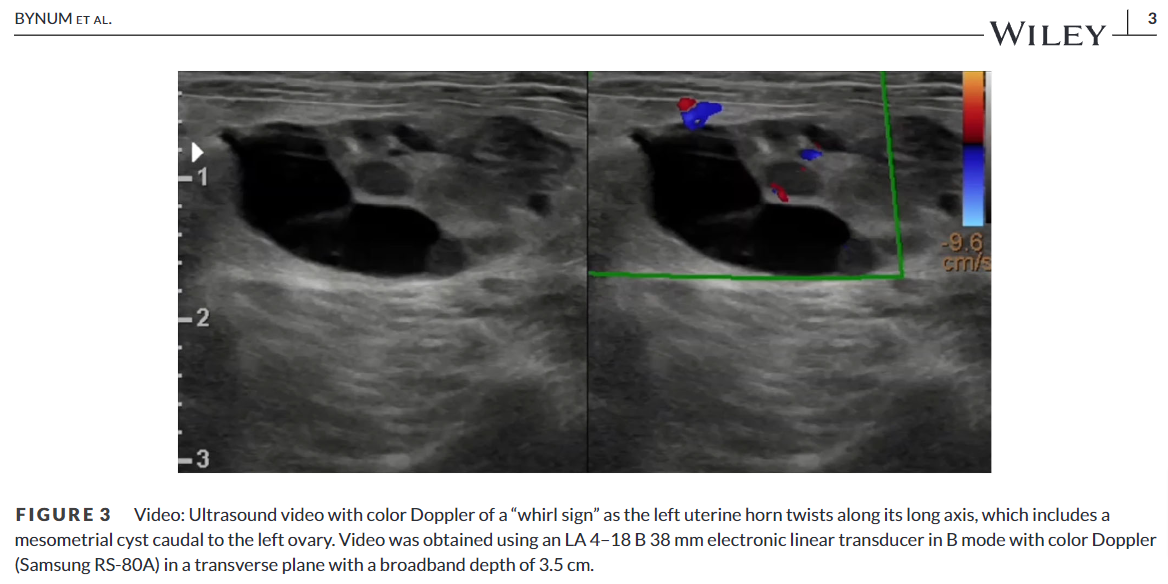

방사선 사진처럼 자궁염전이 발생하면 실제로 대형의 종괴성 병변으로 보이고 초음파 검사에서 cyst 양상으로 보인다. 이번 논문에서는 doppler 사진을 첨부하지 않아 검사의 완결성이 아쉬웠다.

과거 본인의 경험으로 꼬여있는 부분의 doppler 양상이 동맥부의 회오리 양상의 주행상이 보여 자궁 염전으로 의심했던 것, CT상에서 조영제가 주행하는 동맥이 회오리 상으로 보였던 것을 볼 때 그런 특이적 영상이 첨부되었으면 좋았을 것으로 판단된다.